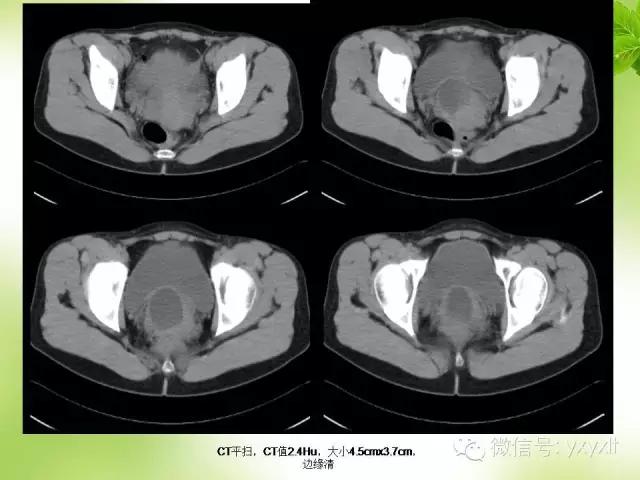

来源:云南省肿瘤医院放射科 病史:患者,女性,31岁,3年前妇检发现盆腔囊肿,经阴道穿刺抽出透亮液体约10ml,以后定期检查,盆腔囊肿无消退。

妇检:阴道穹窿前方扪及约3.0cm×4.0cm的包块,界清,弹性感,活动欠佳,无压痛。

超声:膀胱后壁后上方宫颈前唇及阴道上段区域囊性占位病变,性质待查。

CT:囊肿表现为单房或多房的薄壁水样低密度病灶薄壁囊性肿块,边缘清楚光整。增强扫描未见强化。